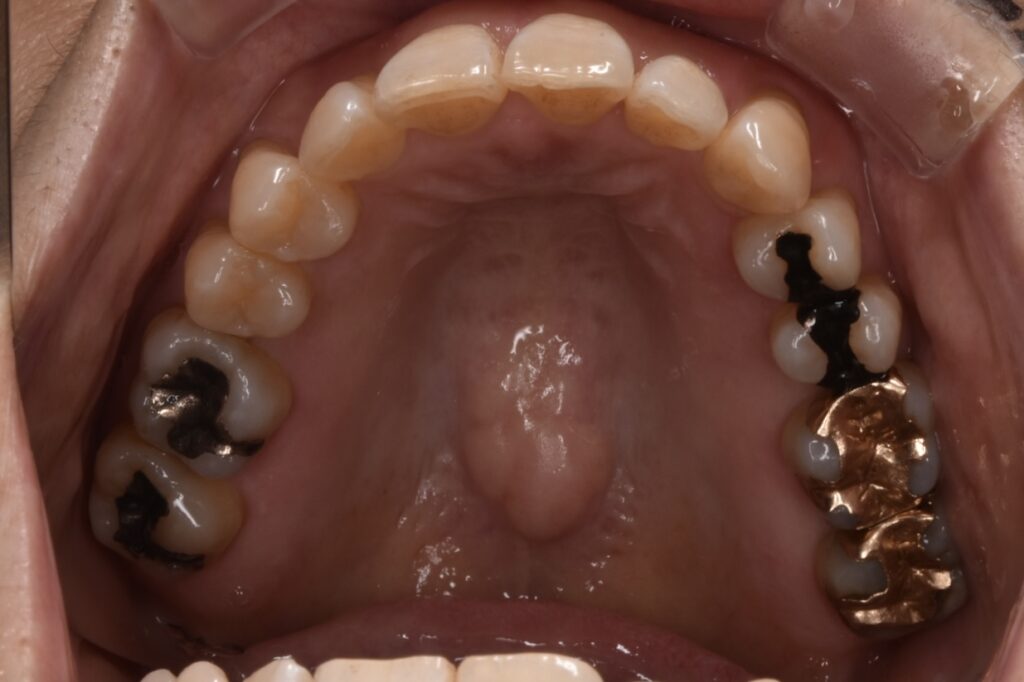

矯正前

前歯を中心に叢生(ガタガタ歯並び)がみられます。

矯正前の横顔や正面、咬合面の写真です。